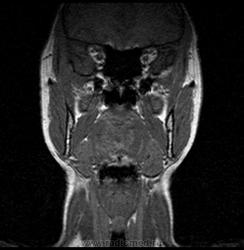

06.06.2011 МРТ - головы и шеи.

Пацентка 36 лет, с жалобами на припухлось в околоушной области справа.

В глубокой доле  правой околоушной железы  на фоне неизмененной паренхимы зона  гетерогенного по Т2, гипоинтенсивного по Т1  с единичными гиперинтенсивными включениями.При контрастировании- накопление контраста диффузное неоднородное и по периферии.Рискну предположить злокачественное образование ( аденокарцинома) с низкой степенью злокачественности( есть капсула, экспансивный рост).Сильно не расстреливайте.

Проблема в том, что перед челюстно-лицевым хирургом стоит распространенность любого объемного процесса, в данном случае все упирается в возмможную травму лицевого нерва и конечно же с дальнейшим его парезом, а ведь женщина  еще молодая. Образование имеет тонкостенную оболочку, по структуре неоднородно, с наличием кальцината, при этом МР-сигнал от окружающих анатомических структур(как костных так и мышечных) не изменен, т.е. об инфильтративном росте речи не идет, в какой то степени доброкачественное. В конкретном случае лицевой нерв с ретромандибулярной веной просто несколько оттеснен.

По гистологии аденома околоушной слюнной железы, но после удаления пока сохраняется парез лицевой мускулатуры, возможно временный.